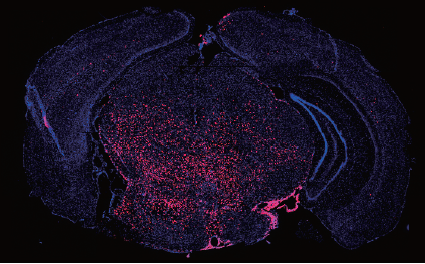

Human ES-derived grafts for repair of radiation injury

Radiation to the brain is a major contributor to poor quality of life among cancer survivors, yet it remains among the most potent tools in cancer therapy. Whole or partial brain radiation is a cornerstone of the treatment of many brain tumors, primary or metastatic, as well as a major component of prophylactic regimens in the treatment of leukemias. Young children are particularly vulnerable to the side-effects of radiation injury and often receive suboptimal radiation doses as a compromise between efficacy and safety. We have shown that radiation to the brain results in loss or significant depletion of the oligodendrocyte progenitor pool in the brain, both in a rat model we developed as well as in human brain tissue samples. We have also developed a scalable protocol for the efficient derivation of oligodendrocyte progenitors from human ES or iPS cells. The cells are well characterized by phenotype markers, gene expression profile and in vitro myelination. In a major effort over the past several years, we optimized rodent brain radiation to mimic the standard high dose fractionated regimen given to patients (50 Gy). The young rats develop cognitive and motor behavioral deficits within several months of treatment. Analysis of the rat brains shows depletion of the oligodendrocyte progenitor pool as well diffuse demyelination. Grafting resulted in structural repair shown histologically and by electron microscopy, as well as in a graft region-specific behavioral improvement. Forebrain grafts improved cognition while cerebellar grafts were required for amelioration of motor balance3. We plan to further optimize the cell culture and in vivo parameters in future pre-clinical studies.

Human ES derived oligodendrocyte progenitors repair radiation-induced demyelination. Illustr. by Susan Weil.